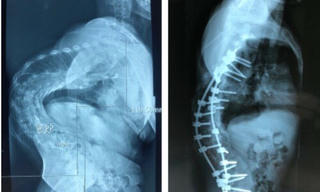

từ khóa: #gù xương